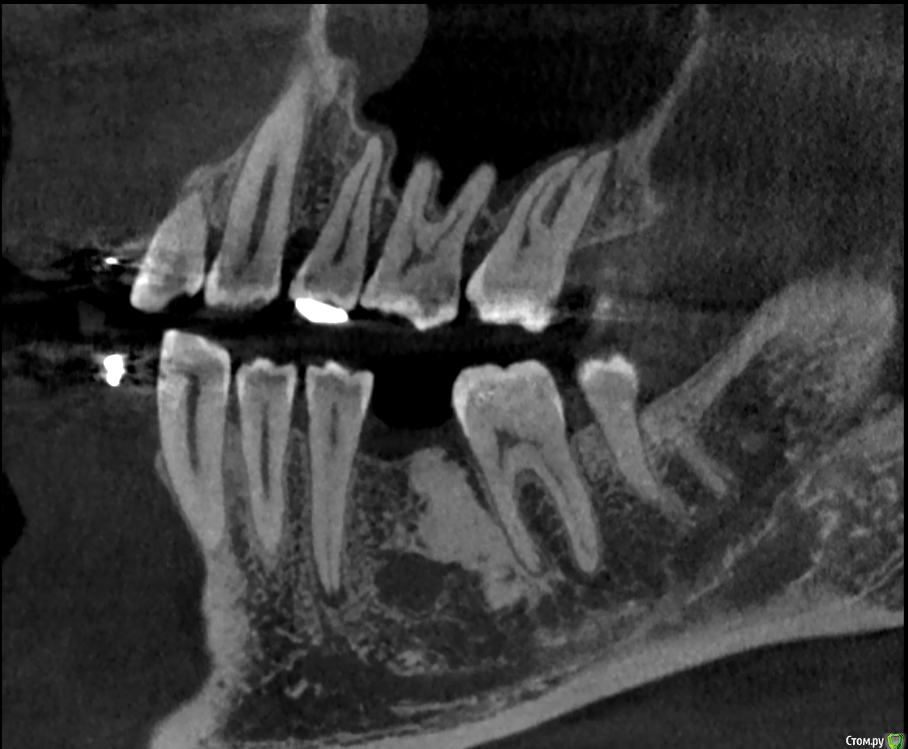

It'sGeorgy Опубликовано 15 января, 2020 Поделиться Опубликовано 15 января, 2020 Здравствуйте!На 2ом прикреплении явно следствие, на 3 и 4 - причина. Вижу 2 варианта развития событий:1: Разрезать, отслоиться. Посмотреть что явилось причиной, удалить причину. Начать готовить ложе под имплантат. 4.0 фрезой провалиться в полость кисты, попытаться извлечь ее через ложе. Поставить имплантат.2: Если через ложе извлечь не удастся, то пойти вестибулярным доступом. Извлечь. Графт, мембрана. 5 мес отдыха. Имплантат. Кто подобным уже занимался, подскажите, насколько перспективен первый вариант? Возможно ли по КТ понять что явилось причиной? На корень не особо похоже. Для остеомы тоже нетипичная картина. Ссылка на комментарий

shy Опубликовано 15 января, 2020 Поделиться Опубликовано 15 января, 2020 (изменено) резидуальная пошел бы через вестибулярный доступ , с графтом или без на усмотрение оперирующего . P.S причину уже удалили до Вас Изменено 15 января, 2020 пользователем shy 1 Ссылка на комментарий